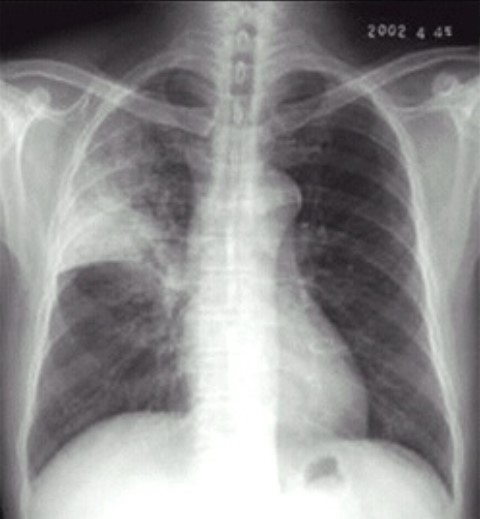

02卷-4.男性,24歲,發(fā)熱、咳嗽、咳痰4天。診斷

A.右上肺不張

B.右上胸膜肥厚

C.右上肺癌

D.右上肺炎

本題答案:D

【該題針對(duì)“ X線-肺炎 ”知識(shí)點(diǎn)進(jìn)行考核】